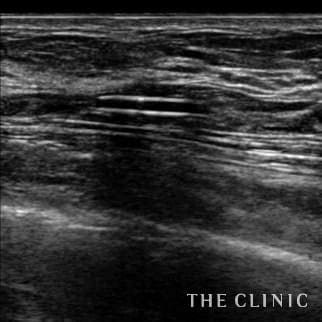

Breast-hip Photo Gallary / No.697

35歳 女性 アクアフィリング(アクアリフト)豊胸のお悩みのアクアフィリング(アクアリフト)豊胸除去

コンデンスリッチ豊胸を行うために、前もってアクアフィリングの除去を行いました。エコーで確認するとかなり厚い被膜が形成されています。 アクアフィリングは生理食塩水で溶解されるとのことで、エコー下に生理食塩水を注入しましたが、なかなか溶解できず、ヒアルロニダーゼも追加してなんとか溶解除去することができました。右側は炎症があった為か、汚く濁った状態でした。治療の概要 アクアフィリング除去+コンデンスリッチ豊胸:乳腺用エコーを用いて、バスト内の状態を確認。その後、生理食塩水でアクアフィリングを溶解する。溶解仕切れない場合には、注射器で吸い出し除去。アクアフィリング の除去後、バストの皮下にコンデンスリッチファット(老化細胞や不純物を取り除いて濃縮させた自己脂肪)を注入。 施術費用 アクアフィリング 除去(会員料金):¥600,000(税込¥660,000)/溶解1部位

コンデンスリッチ豊胸(モニター価格):¥880,000〜(税込¥968,000〜)